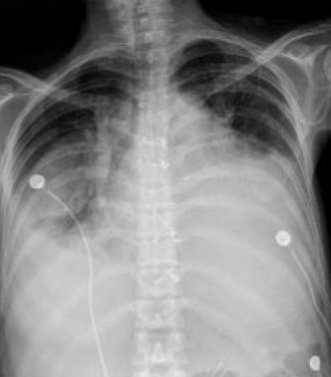

![]() |

Pneumothorax gauche de grande abondance./OpacitĂ© rĂ©ticulo-micronodulaire avec verre dĂ©poli de lâhĂ©michamp pulmonaire gauche avec individualisation dâune volumineuse bulle apical gauche./ | Pneumothorax droit de grande abondance./ OpacitĂ© rĂ©ticulo-micronodulaire dans lâhĂ©michamp pulmonaire droit, avec verre dĂ©poli et prĂ©sence d'une bulle apicale droite importante./ | Pneumothorax gauche modĂ©rĂ©./ OpacitĂ©s rĂ©ticulo-micronodulaires avec zones de verre dĂ©poli Ă©tendues sur lâhĂ©michamp pulmonaire droit./ | Pneumothorax bilatĂ©ral de grande abondance./ PrĂ©sence d'opacitĂ© rĂ©ticulo-micronodulaire avec aspect de verre dĂ©poli sur les deux hĂ©michamps pulmonaires, plus de grande bulle apicale sur le cĂŽtĂ© gauche./ SurĂ©levation de la coupole diaphragmatique droite avec trachĂ©e tirĂ©e vers la droite./ |